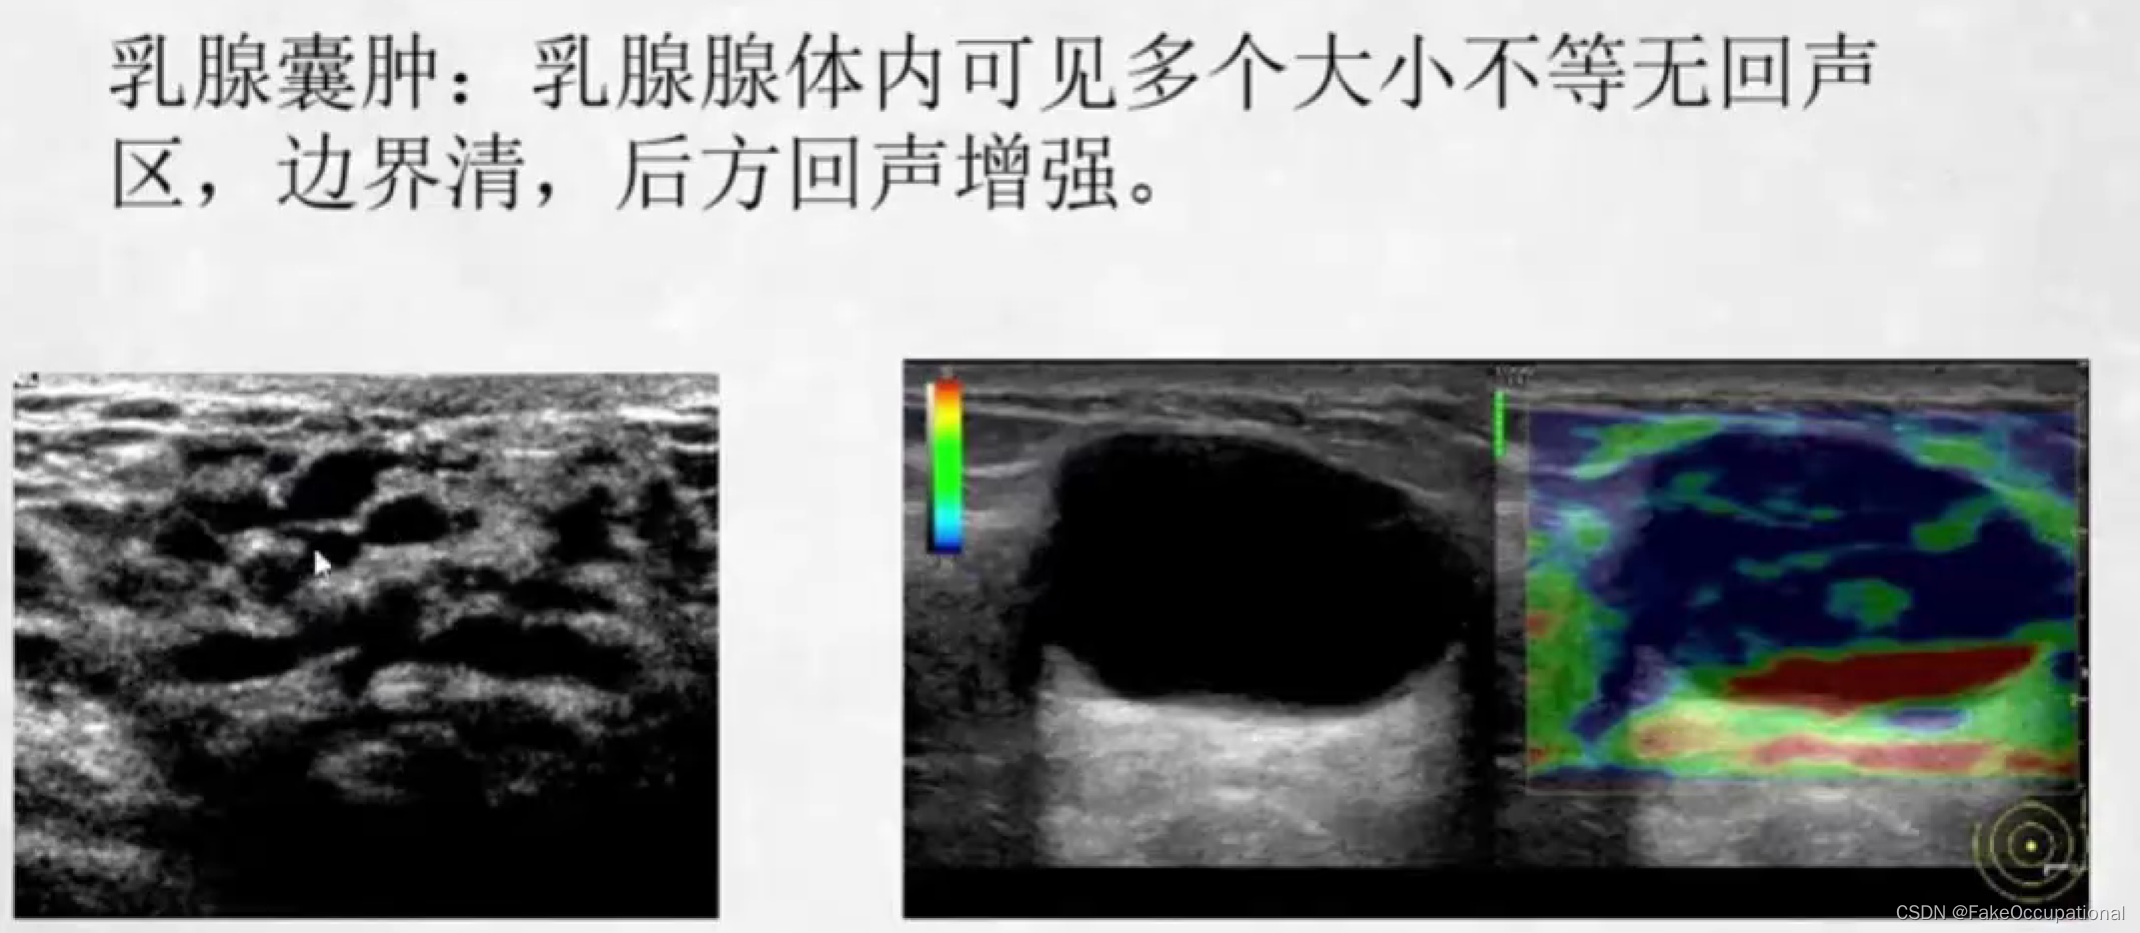

五、后方回声增强

囊肿、脓肿及无回声区的后壁、有些小肿瘤后壁亦可出现

常见乳腺疾病的超声诊断

乳腺增生症

- 女性最常见的乳房疾病好发年龄为30一50岁与内分泌激素紊乱有关(尤其雌激素增高)

- 双侧乳腺周期性胀痛月经前3一4天疼痛加剧月经来潮后症状减轻

- 可触及多个大小不等的质韧结节多呈圆形或条索状